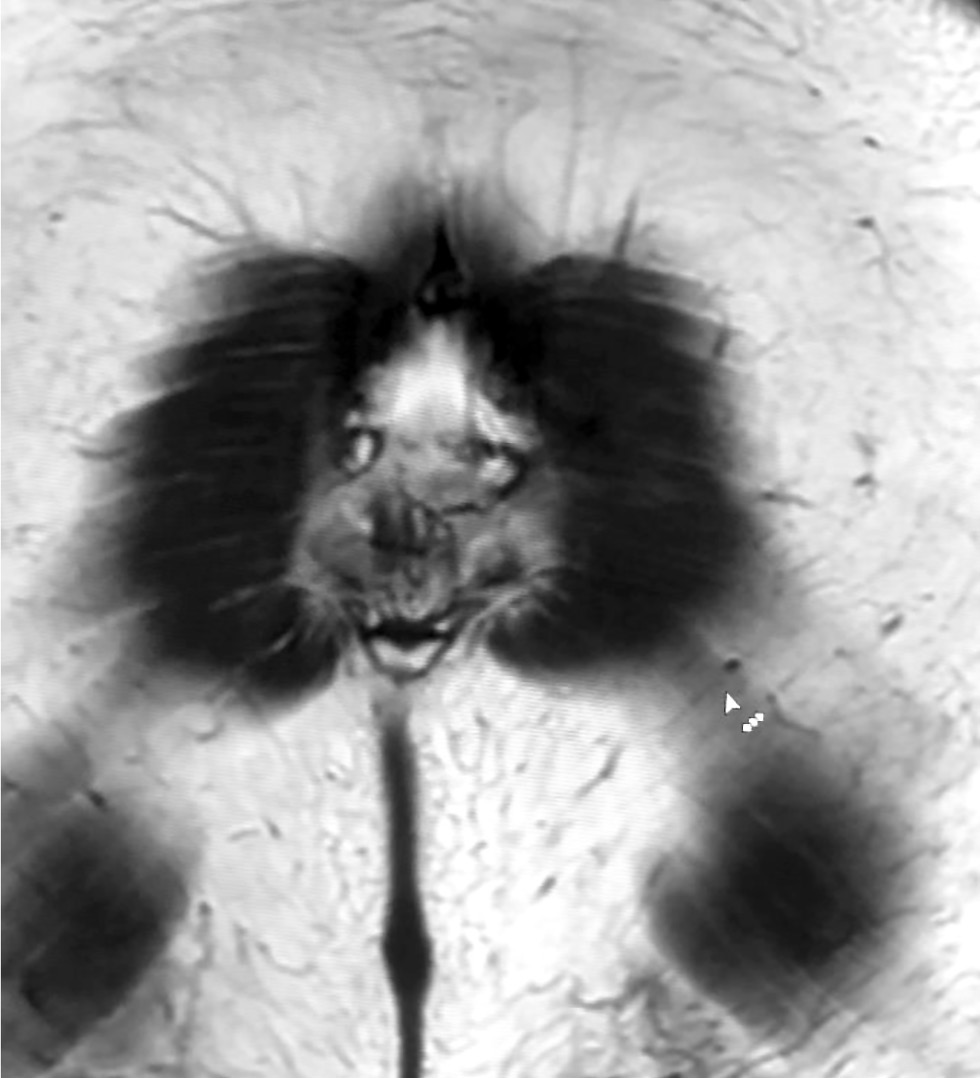

Visual images in radiography: pareidolia as a useful tool for physicians and artificial intelligence

Abstract

This article explored the role of pareidolia in radiography and its potential in improving diagnosis and medical personnel training. Pareidolia is the phenomenon of perceiving familiar patterns in random objects, such as faces on the moon’s surface and animal figures in clouds. In radiography, pareidolia can manifest as recognizable patterns in medical images. This enables radiographers to identify abnormalities and improve their diagnostic skills.

This work aimed to evaluate pareidolia caused by the interpretation of X-ray images and determine its potential applications.

From June to December 2023, a competition was held to create a dataset of pareidolic illusions. Thirty-one individuals participated, including medical imaging specialists who had access to radiographic images. Images from nine additional participants were obtained outside the competition. Overall, 71 images were received. Participants uploaded images using a form on Yandex Forms. Data quality was ensured by clearly defined inclusion and exclusion criteria.

Data analysis revealed that people most frequently perceive human faces, animal snouts, and the heart symbol. These findings indicate the possibility of further research. This article discusses the potential applications of pareidolia in developing neural networks for automated medical image analysis and in educational activities that stimulate creative thinking and association.

Moreover, the article emphasizes the importance of ongoing research in this area to develop effective diagnostic tools and educational programs by expanding the evidence base.